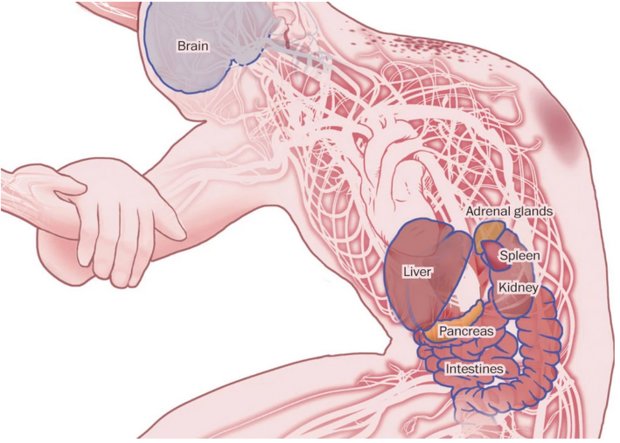

مرحله حمله

ویروس به سلول های ایمنی در جریان خون حمله می کند، و عفونت را به کبد، طحال و گره های لنفاوی انتقال می دهد. ابولا از انتشار اینترفرون، یک پروتئین ساخته شده توسط سلول های ایمنی برای مبارزه با ویروس، جلوگیری می کند.

سلول های ایمنی آلوده از طریق جریان خون یا مجراهای لنفی به دیگر بافت ها و اندام ها، به خارج از طحال و گره های لنفاوی، انتقال می یابند.

اختلالات چند سیستمی

• ابولا یا توسط سلول های آلوده به ویروس یا با پاسخ التهابی شدید بدن، به بسیاری از بافت ها آسیب می رساند.

• اختلال غدد آدرنال، منجر به فشار خون پایین خطرناک و کاهش توانایی تولید هورمون های استروئیدی می شود.

• به بافت های همبند بدن، که نقش سلول های پوشاننده برای حفره ها و سطوح بدن را دارند، حمله می شود.

• نارسایی کبد و کلیه رخ می دهد.

• پانکراس آلوده می تواند منجر به درد شدید شکم شود.

• آسیب روده باعث اسهال و کاهش آب بدن می شود.

مایع در مغز تجمع می یابد. تشنج باعث گسترش خون عفونی و سایر مایعات بدن بیمار می شود.